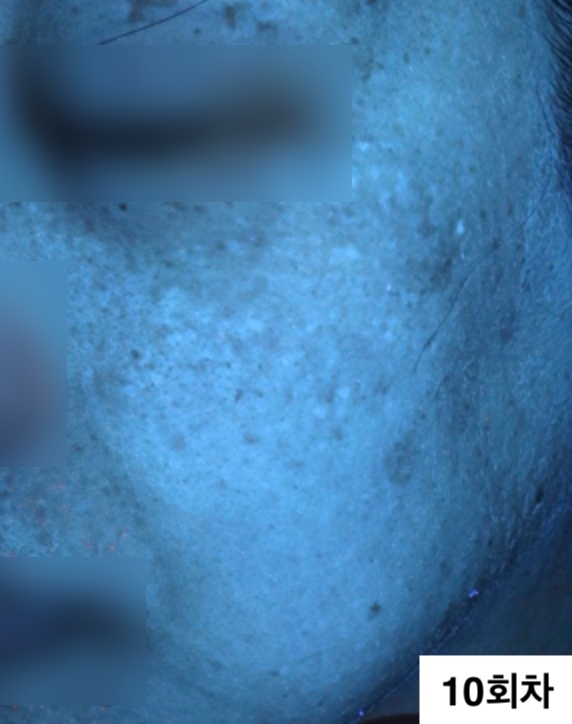

자외선광 1회차 / 10회차

2024.12.24

2025.04.04